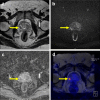

Results: We reviewed 57 original research articles during the period 2016-2021: 14 articles regarding the radiotracer PSMA; 18 articles regarding the primary tumor detection, local tumor staging, managing local recurrence; 17 articles for managing lymph node metastases; and eight articles for managing bone and other distant metastases. PSMA PET could be complementary to mpMRI for primary prostate cancer localization and is particularly valuable for PI-RADS three lesions. PET-MRI is better than PET-CT in local tumor staging due to its specific benefit in predicting extracapsular extension in MRI-occult prostate cancer patients. PET-MRI is likely superior as compared with PET-CT in detecting local recurrence, and has slightly higher detection rates than PET-CT in lymph node recurrence. PET-CT and PET-MRI seem to have equivalent performance in detecting distant bony or visceral metastases.